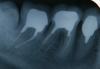

Tasadik Опубликовано 29 мая, 2009 Автор Поделиться Опубликовано 29 мая, 2009 (изменено) Уважаемые врачи, посмотрите пжл снимки, сейчас стоят временные коронки и планируют 4-го июня установить МК. Мне не нравится 35 и 36 зубки. Может я зря паникую, скажите плс Ваше мнение. Изменено 29 мая, 2009 пользователем Tasadik Ссылка на комментарий

Д.С. Опубликовано 29 мая, 2009 Поделиться Опубликовано 29 мая, 2009 35 вообще пустой. Удаляйте вкладки, перепломбировывайте, делайте новые ВКВ Ссылка на комментарий

Tasadik Опубликовано 29 мая, 2009 Автор Поделиться Опубликовано 29 мая, 2009 35 вообще пустой. Удаляйте вкладки, перепломбировывайте, делайте новые ВКВ А состояние 36? вкладка криво или я чего то не понимаю? А вкладку то вынуть возможно? Ссылка на комментарий

Д.С. Опубликовано 29 мая, 2009 Поделиться Опубликовано 29 мая, 2009 А состояние 36? вкладка криво или я чего то не понимаю? А вкладку то вынуть возможно?кривовато и коротковато Вытащить можно Ссылка на комментарий

Tasadik Опубликовано 29 мая, 2009 Автор Поделиться Опубликовано 29 мая, 2009 (изменено) Скажи пжл, а как все это объяснить врачу Ведь мне у него же придется все исправлять Эта клиника считается самая лучшая в городе, да и врач по рекомендации. Как в таком случае указывать на ошибки и недочеты, ведь это его работа а не моя. Может сменить на пол пути врача? Но ведь другие могут и не взяться переделывать работу другого врача. 37-ой нормальный? или тоже... Изменено 29 мая, 2009 пользователем Tasadik Ссылка на комментарий

Д.С. Опубликовано 29 мая, 2009 Поделиться Опубликовано 29 мая, 2009 Скажи пжл, а как все это объяснить врачу Ведь мне у него же придется все исправлять Эта клиника считается самая лучшая в городе, да и врач по рекомендации. Как в таком случае указывать на ошибки и недочеты, ведь это его работа а не моя. Может сменить на пол пути врача? Но ведь другие могут и не взяться переделывать работу другого врача. 37-ой нормальный? или тоже...37, похоже нормальный. А доктор видел эти снимки? Если можно спорить по-поводу пломбировки 6-го, то про его вкладку, а тем более про 5-й... Если 5 он собирается оставлять так, как есть, тогда меняйте доктора Ссылка на комментарий

Tasadik Опубликовано 4 июня, 2009 Автор Поделиться Опубликовано 4 июня, 2009 (изменено) Опять я к Вам за советом. Сегодня была на приеме, собрала сразу обоих и терапевта и ортопеда, показала снимок, сказала что не нравится, ответ следующий: работа ему нравится поскольку в 35-м не пустота, с его слов, а нерентгеноконтрастный цемент, до апекса со слов терапевта добраться невозможно так как там все резорцировано, до лечения штифт стоял на всю длину. 36-й сделал как мог, поскольку глубже нельзя, у меня там два канала сходящихся в один, ножка якобы на самом деле в канале но с другой стороны, поэтому кажется криво, а на самом деле якобы прямо. Еще была сказка о том что рентген зубов делается как-то снизу, поэтому культи кажутся короче а на самом деле они длиннее. Я взяла время до 8-го числа подумать и вот сижу голову ломаю. Помогите советом пжл. Если там действительно цемент, хотя я не верю, но вдруг, это что-то меняет? Изменено 4 июня, 2009 пользователем Tasadik Ссылка на комментарий

АНРОША Опубликовано 9 июня, 2009 Поделиться Опубликовано 9 июня, 2009 Опять я к Вам за советом. Сегодня была на приеме, собрала сразу обоих и терапевта и ортопеда, показала снимок, сказала что не нравится, ответ следующий: работа ему нравится поскольку в 35-м не пустота, с его слов, а нерентгеноконтрастный цемент, до апекса со слов терапевта добраться невозможно так как там все резорцировано, до лечения штифт стоял на всю длину. 36-й сделал как мог, поскольку глубже нельзя, у меня там два канала сходящихся в один, ножка якобы на самом деле в канале но с другой стороны, поэтому кажется криво, а на самом деле якобы прямо. Еще была сказка о том что рентген зубов делается как-то снизу, поэтому культи кажутся короче а на самом деле они длиннее. Я взяла время до 8-го числа подумать и вот сижу голову ломаю. Помогите советом пжл. Если там действительно цемент, хотя я не верю, но вдруг, это что-то меняет?35 абсолютно пустой, никакого "нерентгеноконтрастного" цемента в нем нет... про рентген - очень смеялась... Д.С. абсолютно правильно сказал -надо доктора менять.35 - вкладку вынимать, канал перелечивать и делать новую вкладку. Ссылка на комментарий